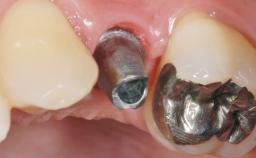

Early Placement of an Implant in a Maxillary Right Central Incisor Site

This 41-year-old female patient was referred to the clinic for the replacement of the right central incisor, since the tooth had developed a root fracture in the long axis that made extraction necessary. The healthy, non-smoking patient was first seen with the tooth still in place. A detailed Esthetic Risk Assessment was performed.The patient was worried about her dental esthetics and had high expectations for a successful treatment outcome from an esthetic point of view. The patient had a medium lip line that displayed parts of the gingiva in the anterior maxilla upon smile.

Placement Protocol Early or late implant placement

Bone Volume Deficient horizontally, allowing simultaneous augumentation